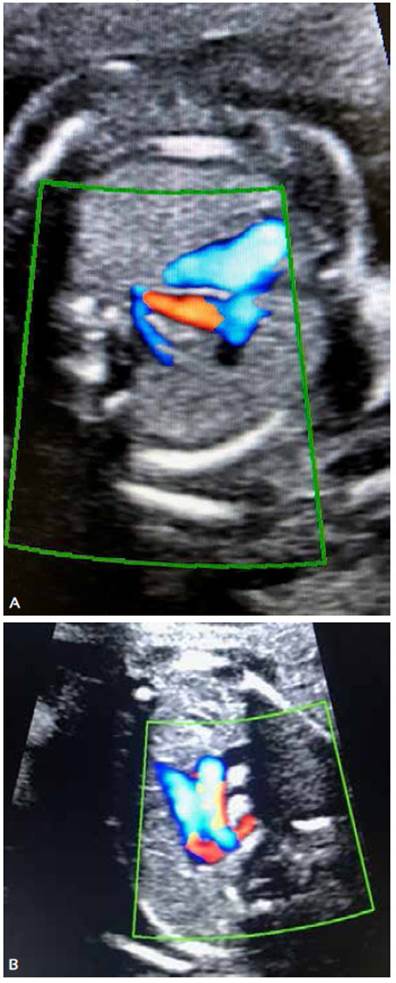

Acudió a las 20 semanas de gestación para ecografía anatómica fetal, visualizándose a nivel del corte de tres vasos tráquea, un vaso retro-traqueal, con sospecha de arteria subclavia derecha aberrante. Se completó el estudio anatómico sin identificarse alguna otra alteración estructural cardiaca o extracardiaca. El sexo era masculino. Figura 2 A y B.

Figura 2 A y B. A nivel de corte de 3VT con función Doppler se visualiza vaso retrotraqueal correspondiente con ARSA.